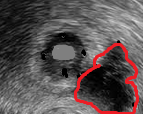

Μακροσκοπική εμφάνιση ωοθήκης μετά ολική υστερεκτομή σε γυναίκα 46 ετών με μετάχρονες ωοθηκικές μεταστάσεις που διαγνώστηκαν δύο χρόνια μετά δεξιά ημικολεκτομή για καρκίνωμα ανιόντος κόλου. Η μακροσκοπική εμφάνιση του ωοθηκικού όγκου αναδεικνύει κυστικές και στερεές περιοχές (Ευγενική παραχώρηση Dr. V. Penopoulos)